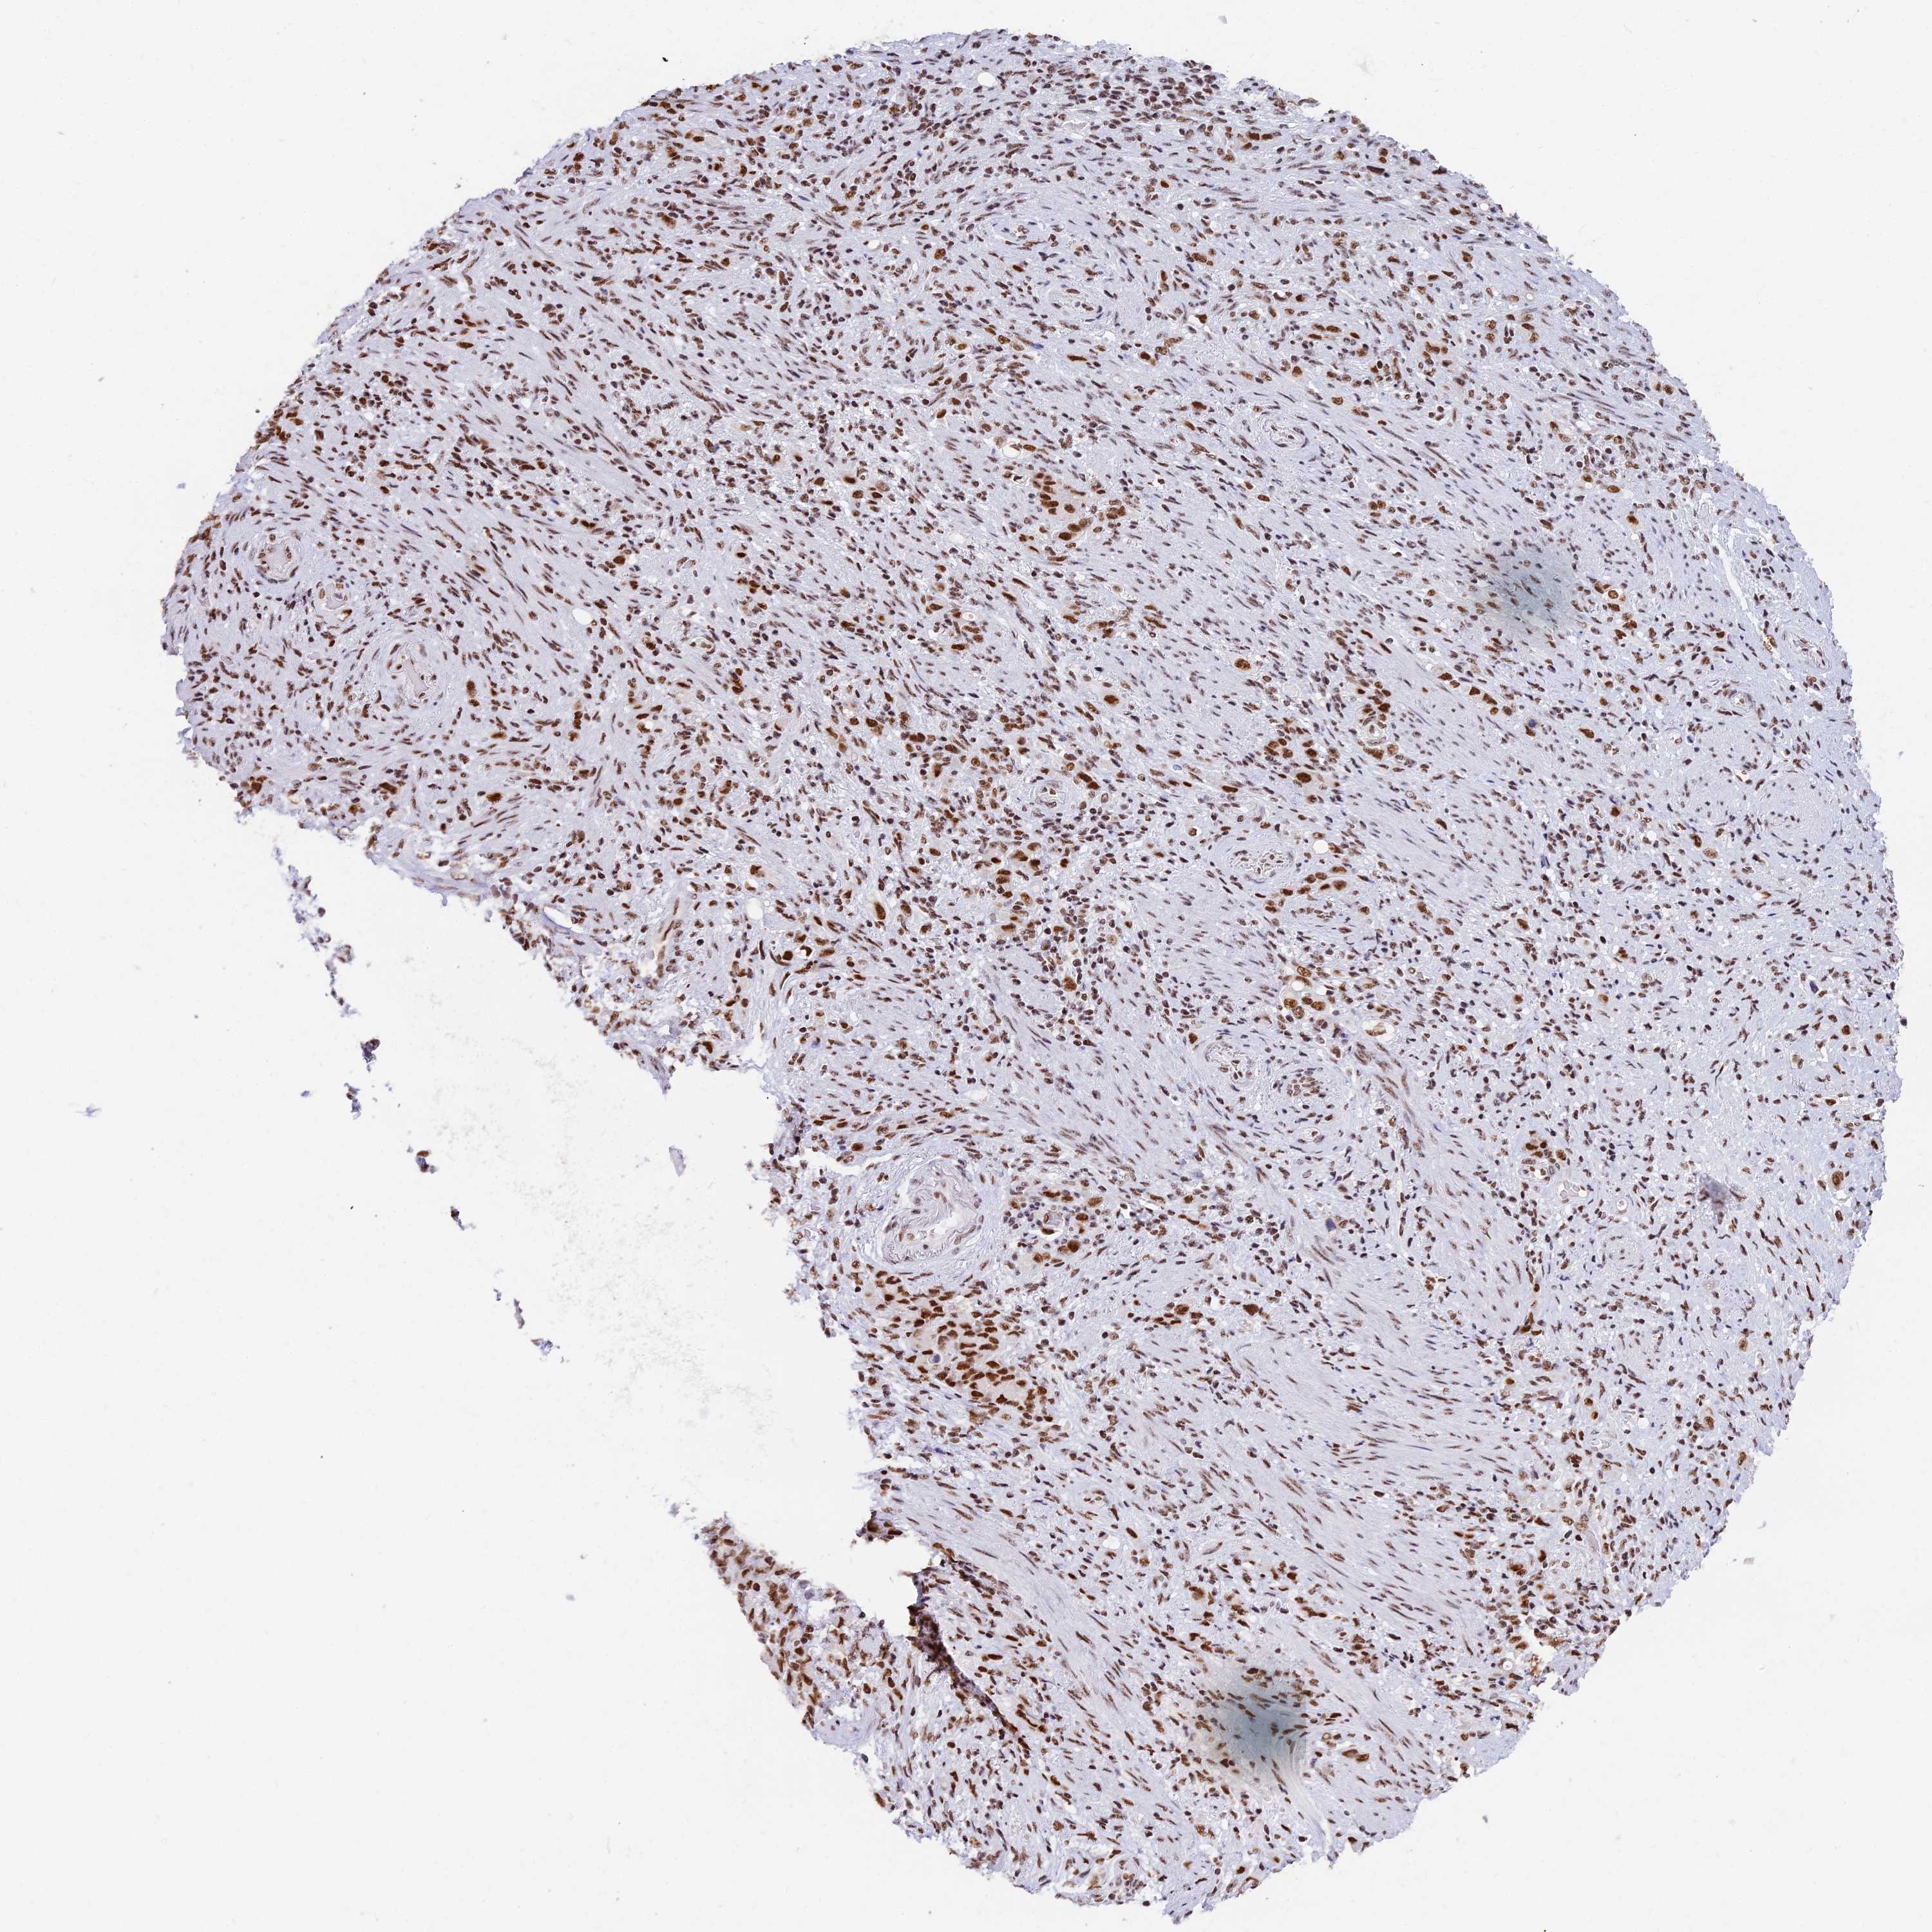

STOMACH CANCER - Protein expressioni

A mouse-over function shows sample information and annotation data. Click on an image to view it in a full screen mode. Samples can be filtered based on level of antibody staining by selecting one or several of the following categories: high, medium, low and not detected. The assay and annotation is described here.

Note that samples used for immunohistochemistry by the Human Protein Atlas do not correspond to samples in the TCGA dataset.

Antibody stainingi

Antibody staining in the annotated cell types in the current human tissue is reported as not detected, low, medium, or high, based on conventional immunohistochemistry profiling in selected tissues. This score is based on the combination of the staining intensity and fraction of stained cells.

Each image is clickable and will lead to virtual microscopy that enables deeper exploration of all samples and also displays staining intensity scores, fraction scores and subcellular localization as well as patient and tissue information for each sample.

Antibody HPA042388

Staining

High

Medium

Low

Not detected

Intensity

Strong

Moderate

Weak

Negative

Quantity

>75%

75%-25%

<25%

None

Location

Nuclear

Cytoplasmic/membranous

Cytoplasmic/membranous,nuclear

Adenocarcinoma, NOS